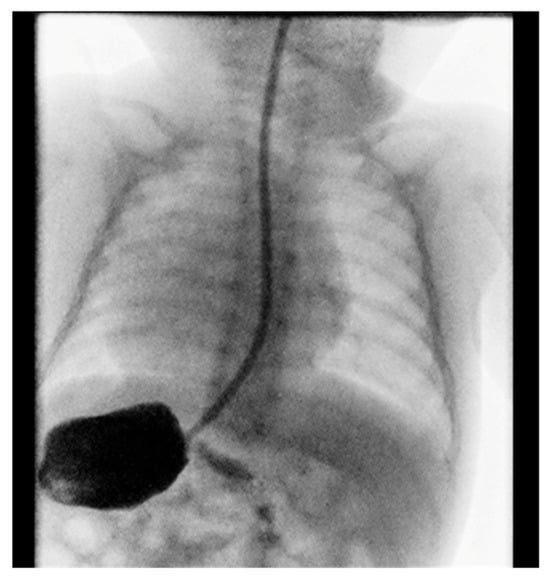

Contrast imaging of the esophagus and stomach shows a normal presentation of the esophagus with the stomach positioned on the right (Figure 2).

Gastroduodenal radiography with contrast showed stomach in the right hemiabdomen. Stomach and duodenum had normal structure and motility. There were no signs of hiatus hernia or gastroesophageal reflux, and there were no obstructions to the passage of contrast fluid.

Figure 2. Position of the stomach on the right.